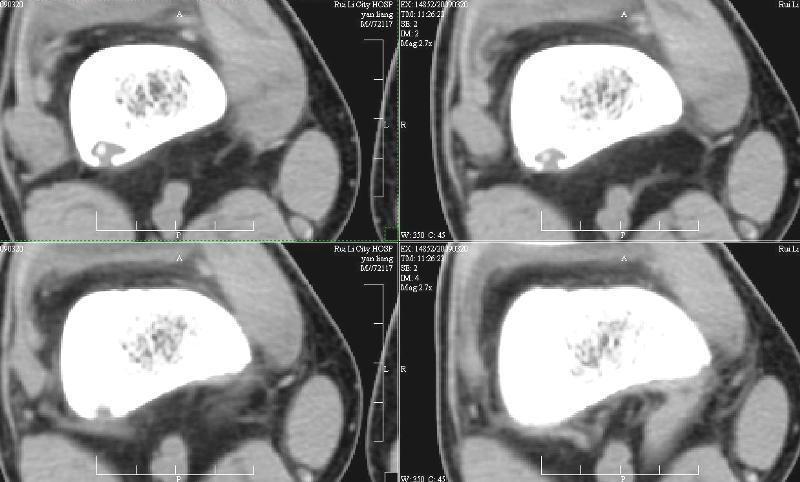

ct:右侧股骨下段后份局限性骨质破坏并病灶区细点状高密度影,性质?骨tb可能性大,软骨瘤、纤维骨皮质缺损及其它待除外,建议结合临床及相关检查考虑。 2、右膝关节腔少量积液。